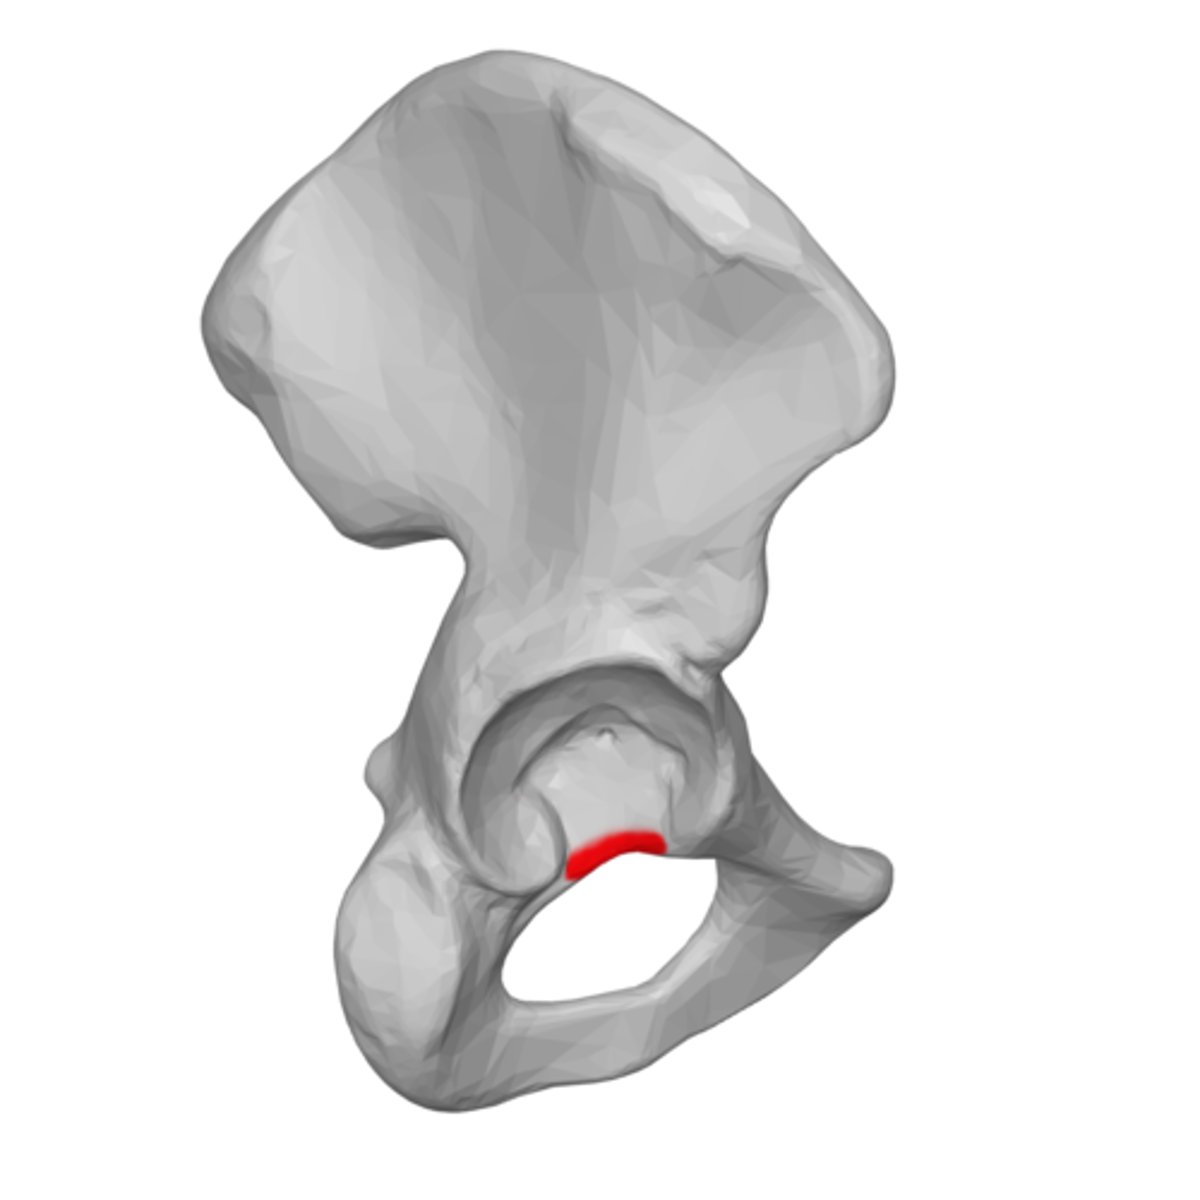

acetabular notch

deep notch in the inferior part of the brim